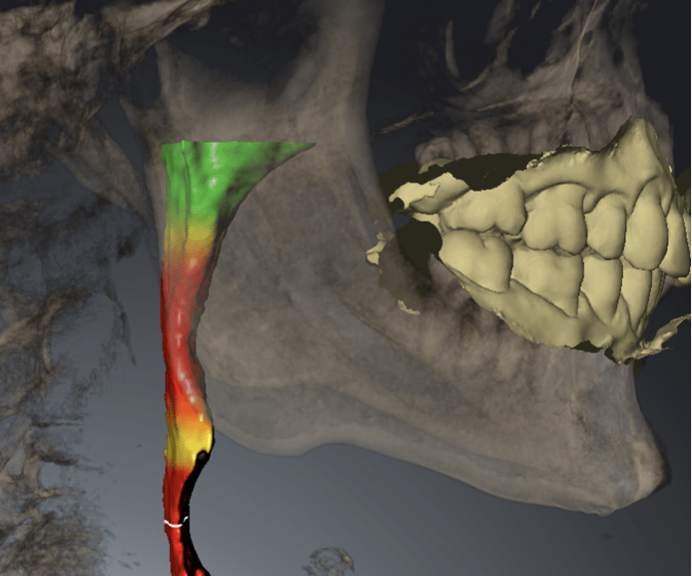

睡眠時無呼吸症 当院では耳鼻科の先生と連携し、睡眠時無呼吸症のための治療を行っております。日本では睡眠時無呼吸症の潜在患者が300万人もいると言われており、海外では生命予後に影響する疾患として認知されています。特に歯科で行う治療には、気道を閉塞させる可能性もあり、それらに配慮した治療を行うことが求められております。当院で採用するSICAT AIRというソフトで気道の状態を3次元的に確認することもできます。気になる方はスタッフにお尋ねください。